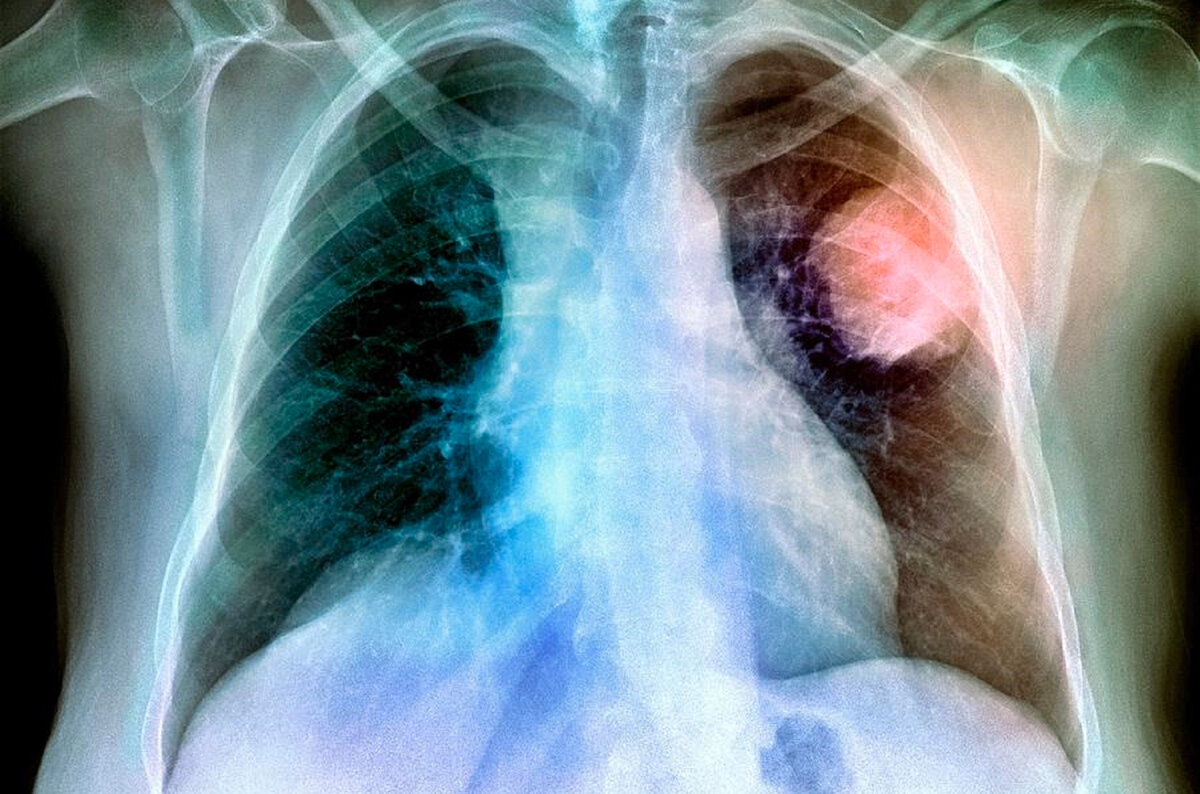

Более точным методом диагностики рака легкого является рентгенография органов грудной клетки в двух проекциях.

При подозрении на опухолевое поражение органов грудной клетки по данным флюорографии и рентгенографии, всем без исключения пациентам требуется проведение уточняющего метода исследования - компьютерной томографии органов грудной клетки.

Наиболее доступным высокоинформативным методом диагностики рака легкого является компьютерная томография (КТ) органов грудной клетки с контрастированием. С помощью этого метода можно выявить даже опухоль небольших размеров, а также оценить состояние регионарных лимфоузлов. Пожалуй, единственным недостатком метода является лучевая нагрузка, которая постепенно снижается на более современном оборудовании, но всё ещё слишком высокая, чтобы использовать этот метод для ежегодного скрининга. Показанием для назначения КТ с контрастированием является подозрение на рак легкого.